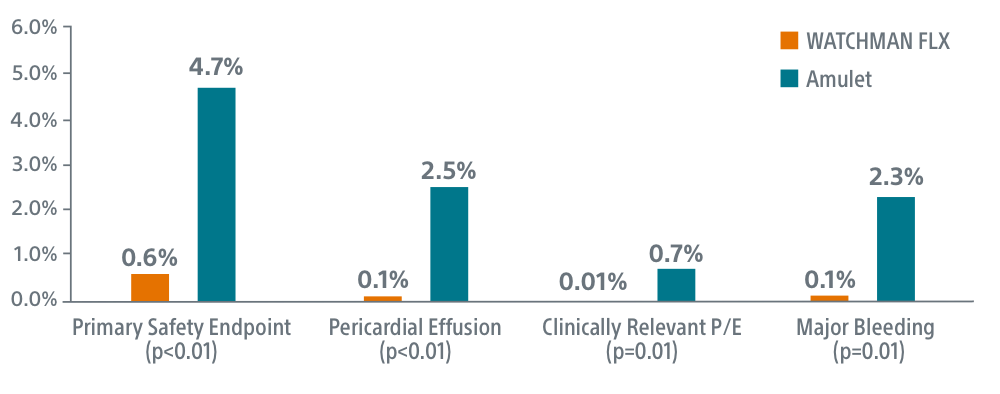

Safety Endpoint

Safety endpoint was the occurrence of death, stroke, major bleeding, myocardial infarction, major vascular complications, device embolization, or pericardial effusion within 7 days post-procedure.

Key Results

Safety

- WATCHMAN FLX superior on primary safety endpoint (0.6% FLX vs 4.7% Amulet, p<0.01)

- WATCHMAN FLX superior on overall pericardial effusion/tamponade (0.1% FLX vs 2.5% Amulet, p<0.01)

- WATCHMAN FLX superior on clinically relevant pericardial effusion/tamponade (0.01% FLX vs 0.7% Amulet, p=0.01)

- WATCHMAN FLX superior on peri-procedural major/intracranial bleeding (0.1% FLX vs 2.3% Amulet, p=0.01)

- 0 device embolizations occurred with WATCHMAN FLX vs. 15 with Amulet

- WATCHMAN FLX demonstrated lower DRT than Amulet (1% vs 1.6%)

- No difference was observed for death or stroke between groups

Simplicity

WATCHMAN FLX showed a trend towards higher procedural success (p=0.08). Procedural success was achieved in 99.9% of WATCHMAN FLX patients (99.4% for Amulet, P=0.08)

Seal

WATCHMAN FLX showed a trend towards more frequent appendage occlusion (leaks >5mm; p=0.06). WATCHMAN FLX demonstrated fewer peri-device leaks >5mm than Amulet (0.01% vs 0.34%, p=0.06)